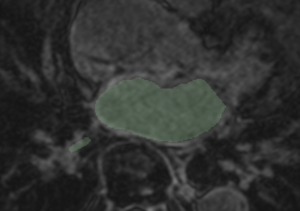

Example 3

Checker-filter: Pre and registered post LGE images Pre segmentation overlaid on registered post LGE Pre segmentation overlaid on registered post LGE

CARMA VecReg Check3.png

CARMA VecReg Seg3.png

CARMA VecReg Seg3-2.png